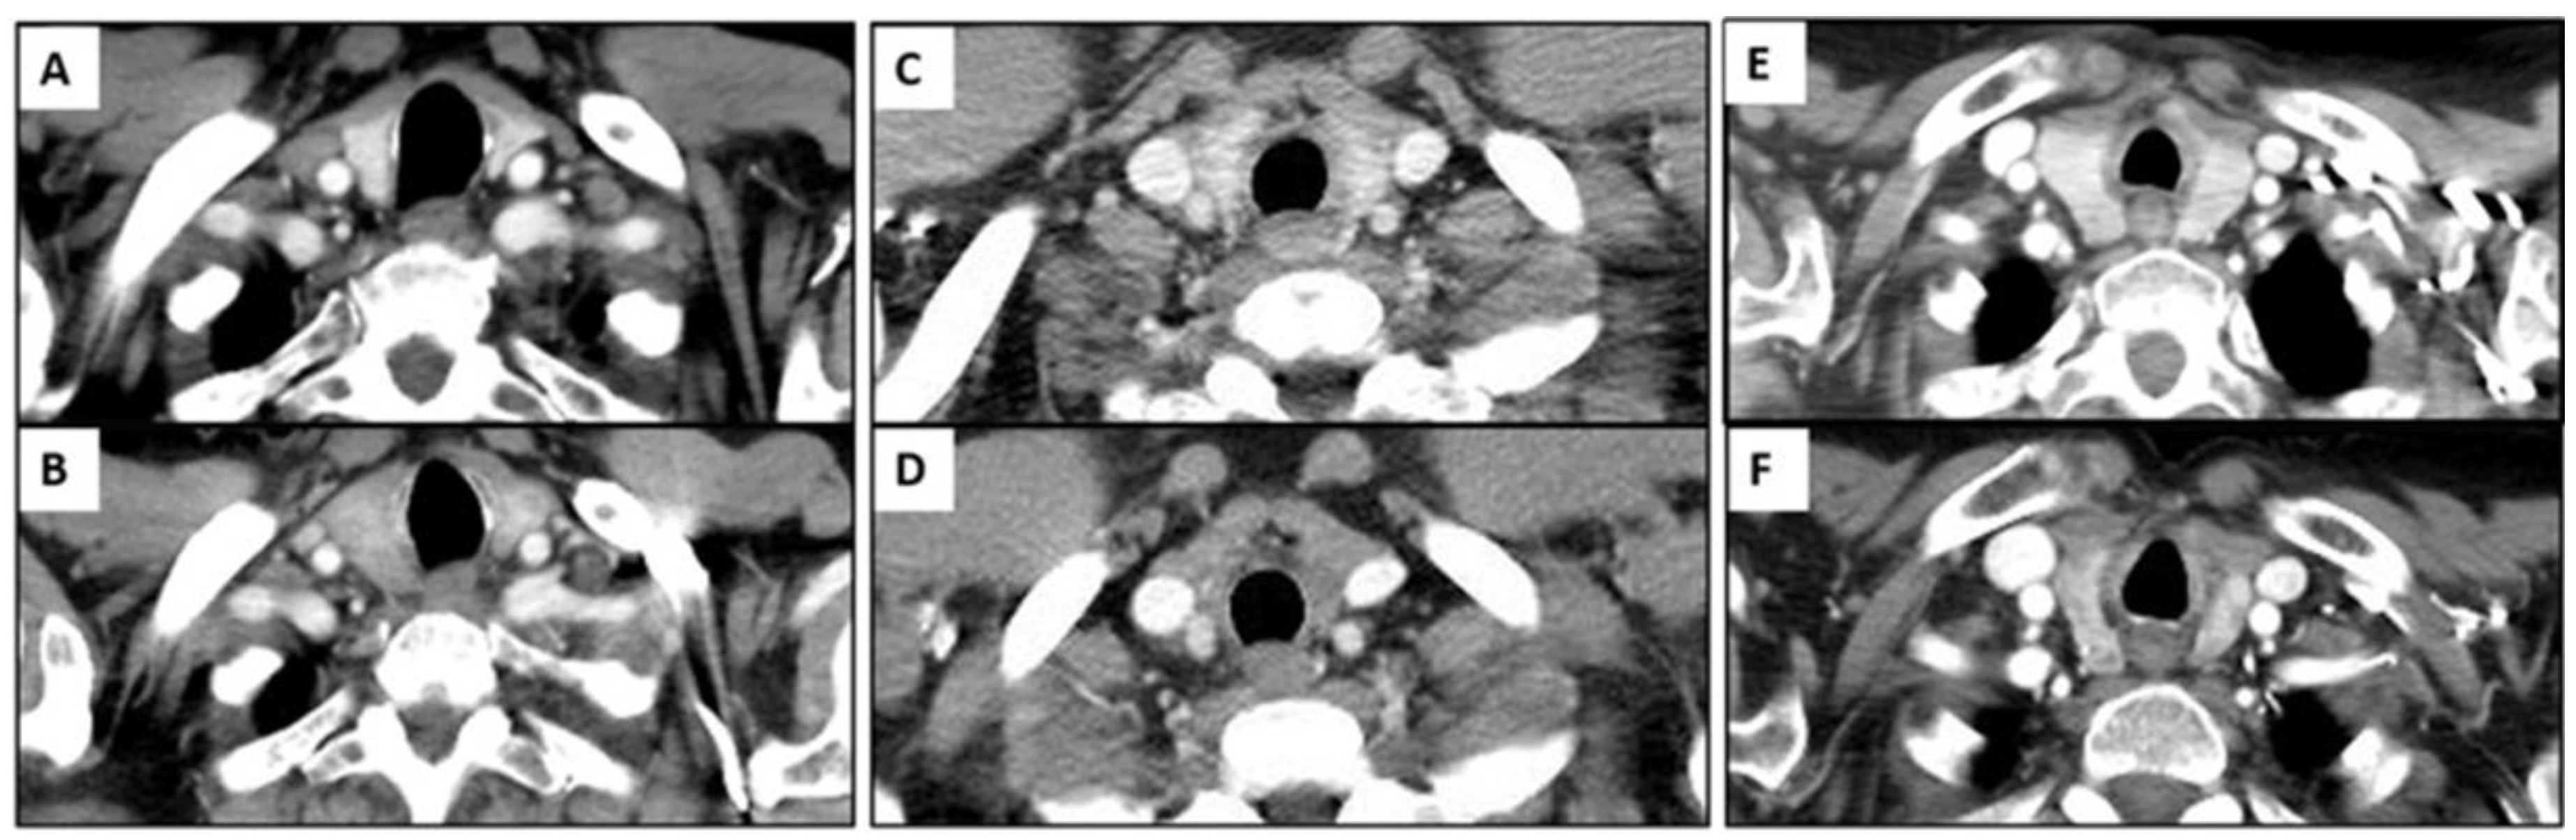

There were 50 patients (50/534, 9.4%) who showed imaging findings indicative of thyroiditis during ICI therapy (Figure 1). The median time from the initiation of therapy to the first CT scan with positive imaging findings was 9.5 weeks (range: 0.9–87.4 weeks). The most common CT finding for thyroiditis was diffuse hypodense attenuation of the thyroid gland, which was seen in 36 patients (36/50, 72%); 15 of these patients also demonstrated enlargement of the thyroid gland and 12 patients demonstrated atrophy (Figure 1). The heterogeneous attenuation of the gland was noted in 12 patients (12/50, 24%), with accompanying enlargement in 7 patients and atrophy in 1 patient (Figure 2). Among the 12 patients with heterogeneous enlargement, 3 patients also had a diffuse increased FDG uptake on PET/CT. Two patients (2/50, 4%) did not show any morphologic changes with the CT scan but had a diffuse increased FDG uptake of the thyroid gland on PET/CT (Figure 3). There were no significant differences in the demographic and clinical parameters between patients with and without findings suggestive of thyroiditis (Table 1)

Figure 2.

Imaging findings of immune-related thyroiditis from chest CT scan. (A,B) A 75-year-old man with advanced lung cancer treated with nivolumab monotherapy. There was interval development of enlarged thyroid gland with diffuse hypoattenuation after 4 weeks of therapy (B) compared to the baseline image (A). (C,D) A 79-year-old woman with advanced lung cancer treated with pembrolizumab monotherapy. There was interval significant atrophy of thyroid gland with diffuse hypoattenuation after 7.1 weeks of immunotherapy (D) compared to the baseline image (C). (E,F) A 78-year-old woman with advanced lung cancer treated with nivolumab monotherapy. There was interval atrophic change in thyroid gland with heterogeneous attenuation after 13.4 weeks of therapy (F) compared to the baseline image (E).